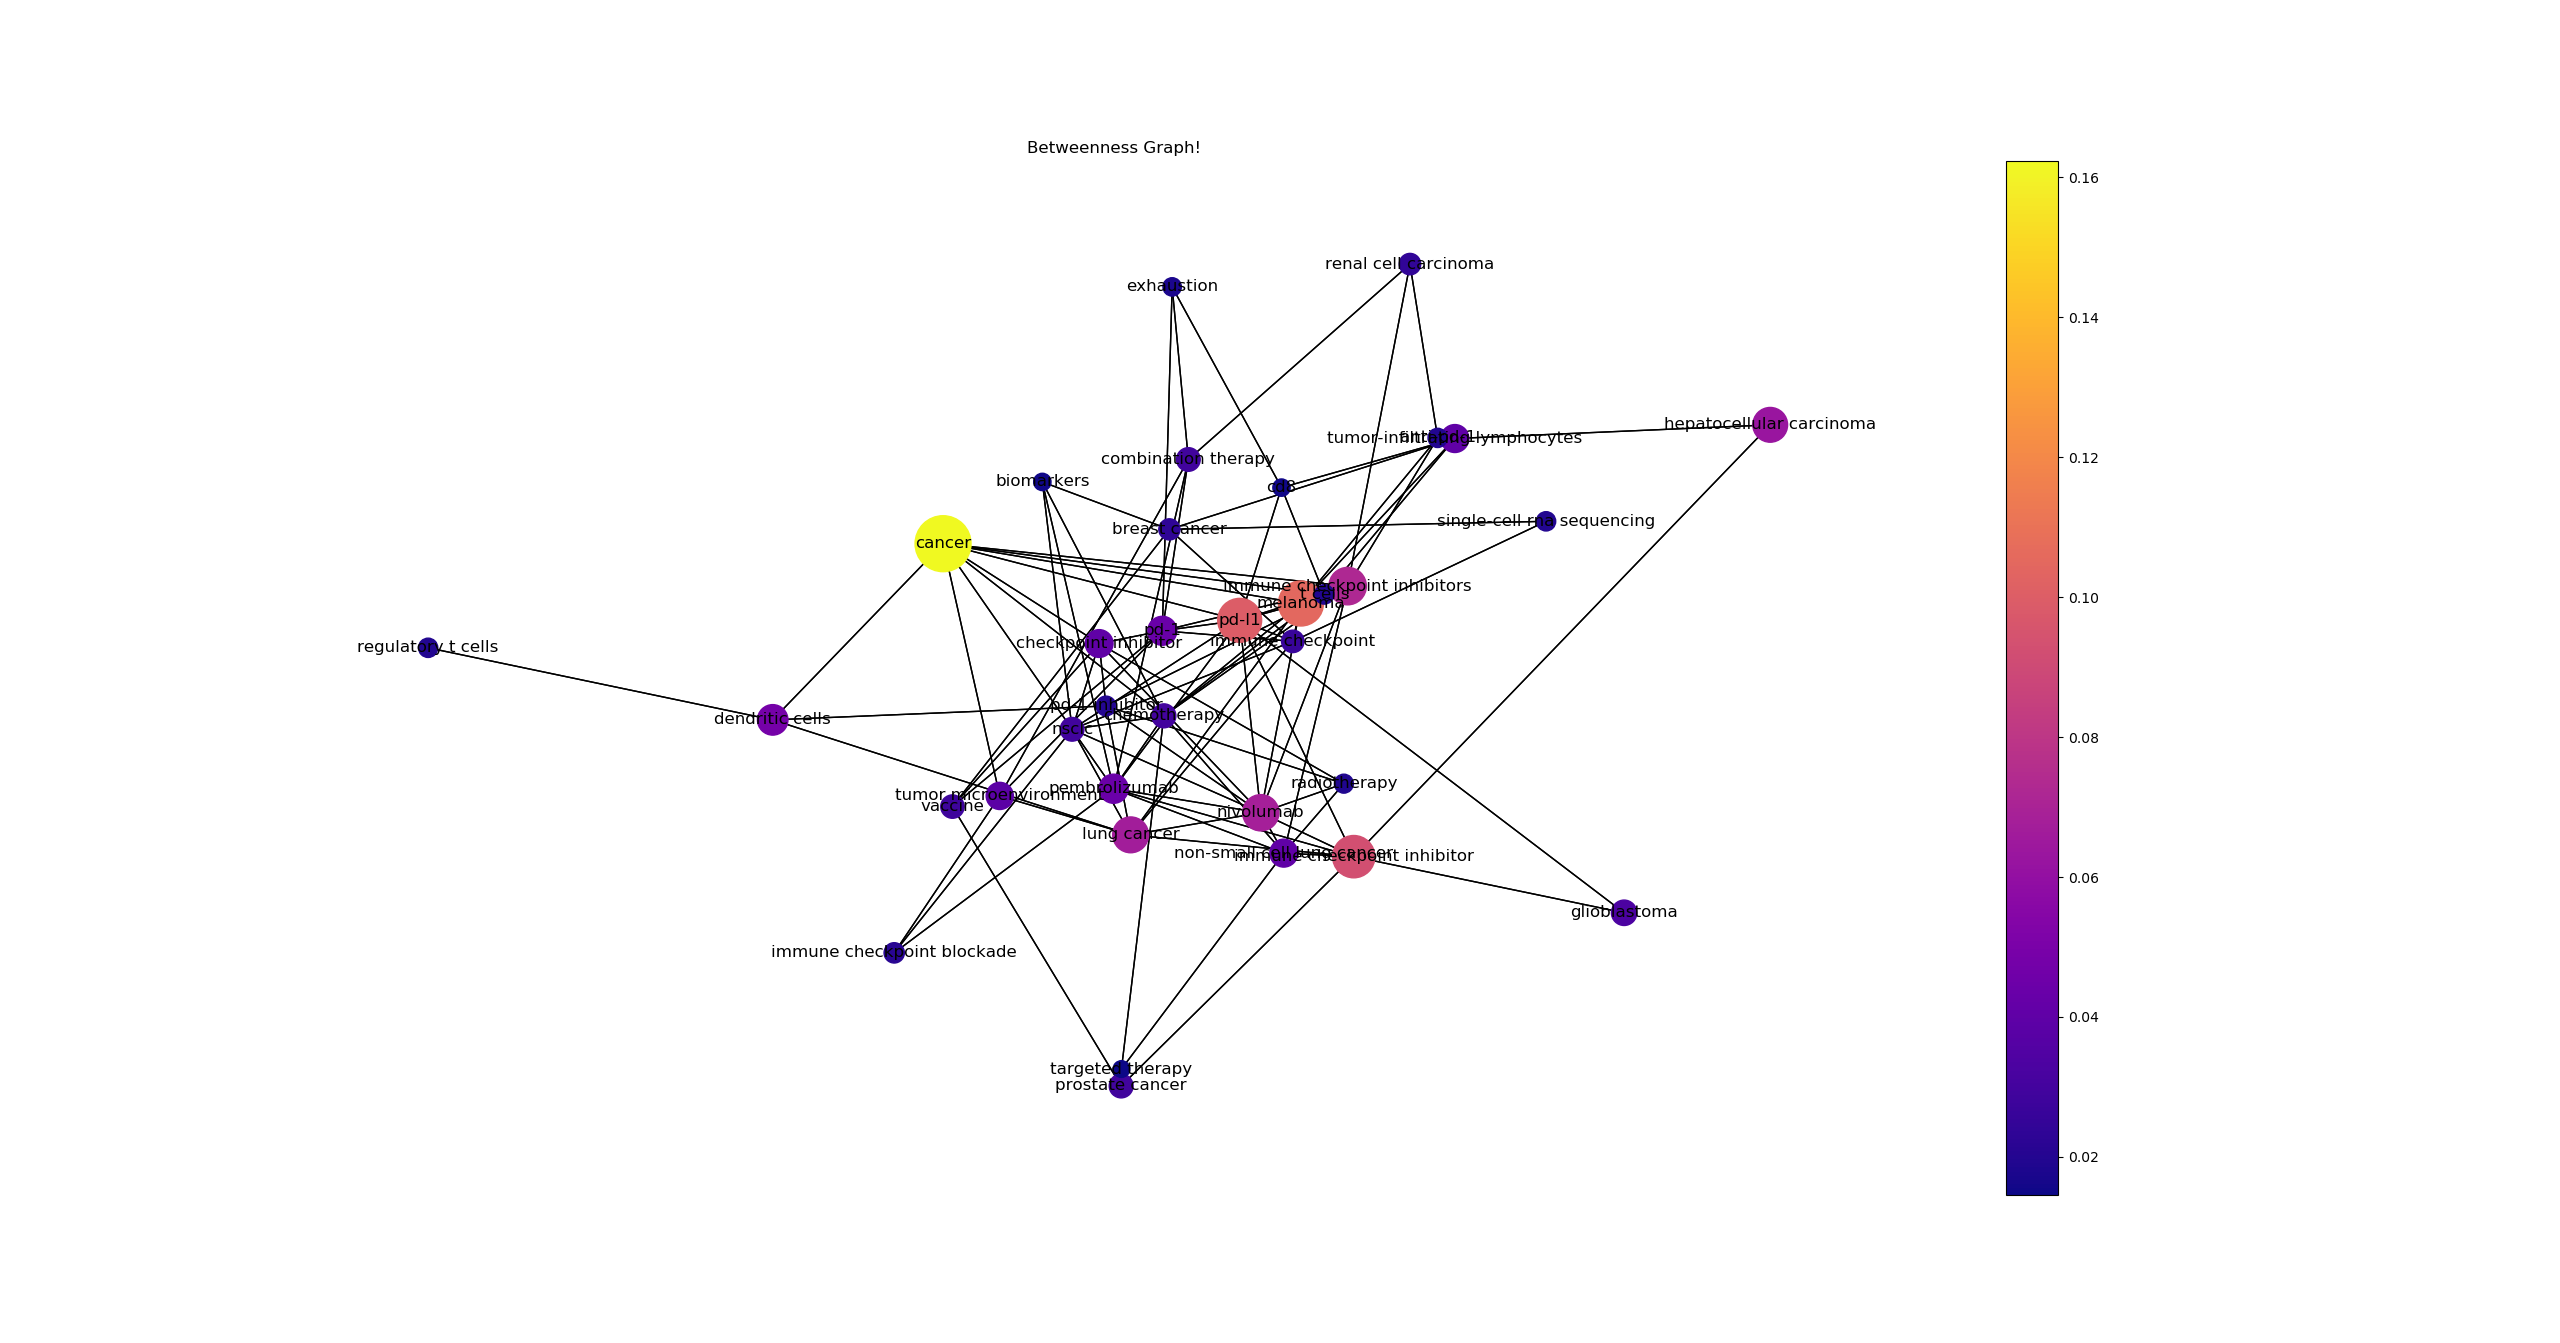

결과

- 데이터 셋에서 100개의 논문 중 상위 5프로의 키워드를 기반으로 도출된 BC(Betweenness_centrality) 그래프